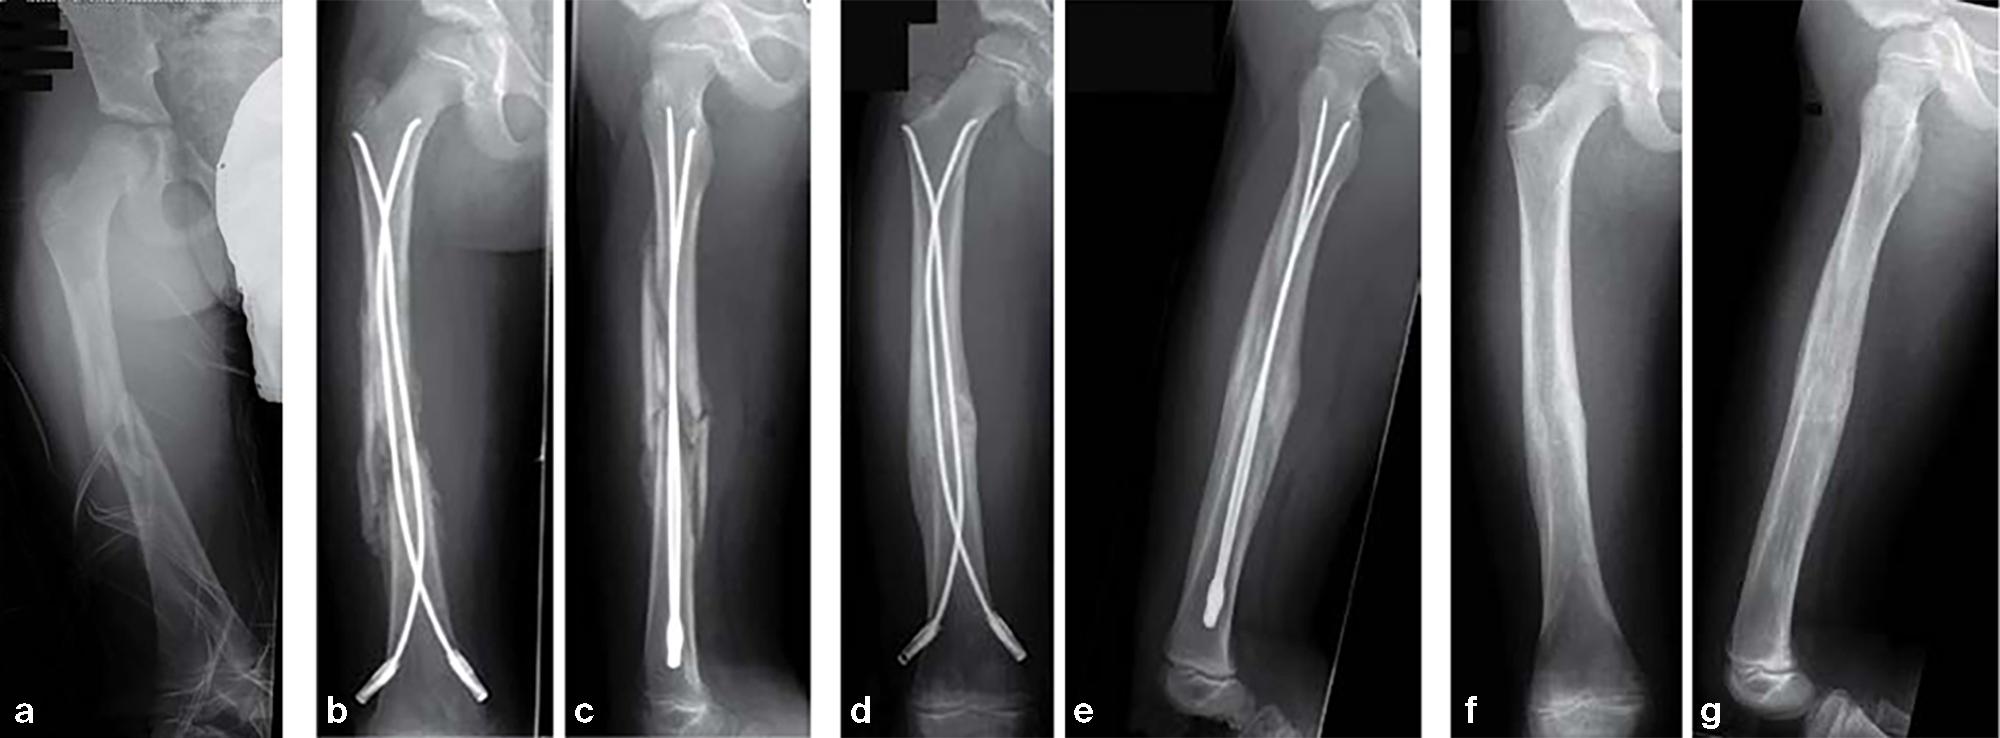

12-year-old boy; snow-board injury long spiral proximal femoral fracture (32D/5.1) primary indication for operation with ESIN and End Cap.

Fig 14a-b: Injury x-rays.

Fig 14c-d: Postoperative x-rays show a correct alignment and length. Fixation with 3.5 mm TEN and End Caps was performed.

Fig 14e: This detail view shows the correct positioning of the End Caps.

Fig 14f-g: 4 1/2 weeks postoperative a good callus and correct alignment was visible, full weight bearing was allowed.